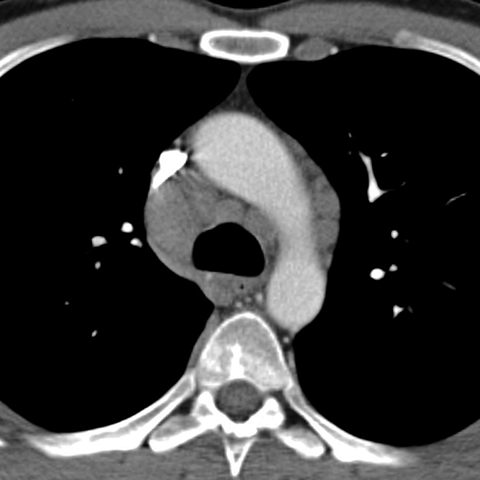

Mediastinal Lymph Nodes in NHL (Axial CT) [2 of 4]